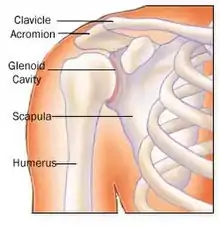

The shoulder is a complex mechanism involving bones, ligaments, joints, muscles, and tendons.

The cuff is responsible for stabilizing the glenohumeral joint to allow abduction and rotation of the humerus. When trauma occurs, these functions can be compromised. Because individuals are dependent on the shoulder for many activities, overuse can lead to tears, with the vast majority being in the supraspinatus tendon.